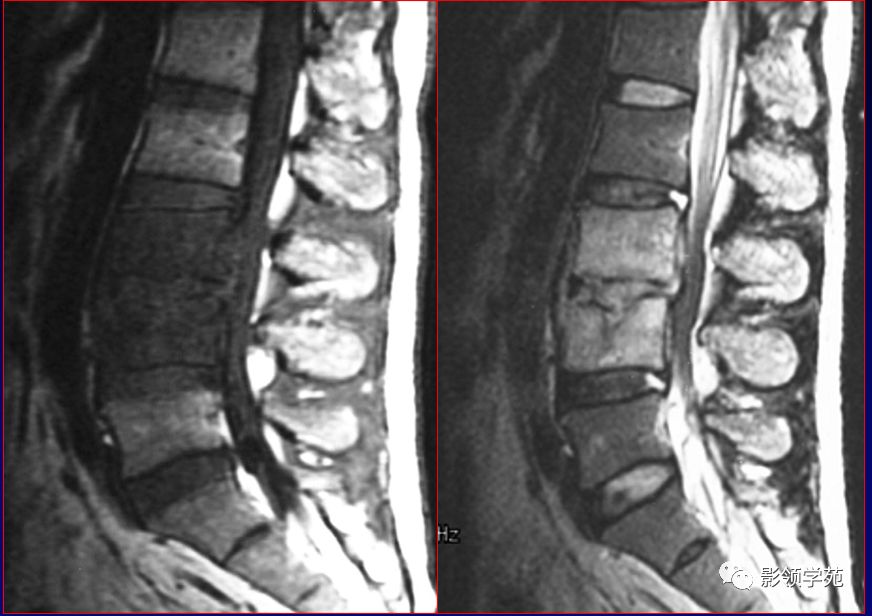

图片来源于网络,如有侵权,请联系删除